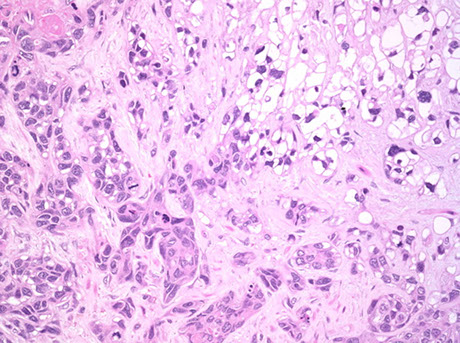

Use of immunohistochemistry in diagnosis of germ cell tumor (GCT). A, A mixed GCT with embryonal carcinoma and yolk sac tumor (YST) components. B, Immunostain of OCT4 is positive in the embryonal carcinoma, negative in the YST. C, Immunostain of GPC3 is positive in the YST and negative in the embryonal carcinoma [2]

[2]